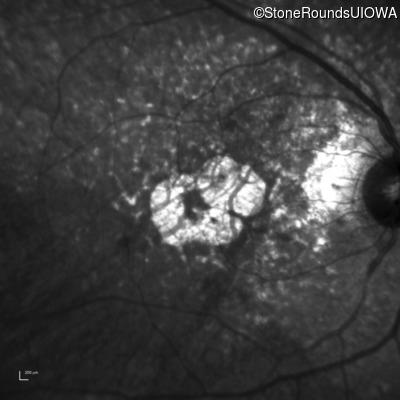

Pattern Dystrophy (IIC)

Age at visit: 62 years

This 62 year old man first noted mild distortion in his vision in his 30's, but has always been correctable to 20/20. One year ago an optometrist told him there were pigment abnormalities in his macula.

Diagnosis & molecular findings

Disease Gene Allele 1 variant(s) Allele 2 variant(s) Inheritance mode

Pattern Dystrophy PRPH2 Lys153Glu AAG>GAG   AD